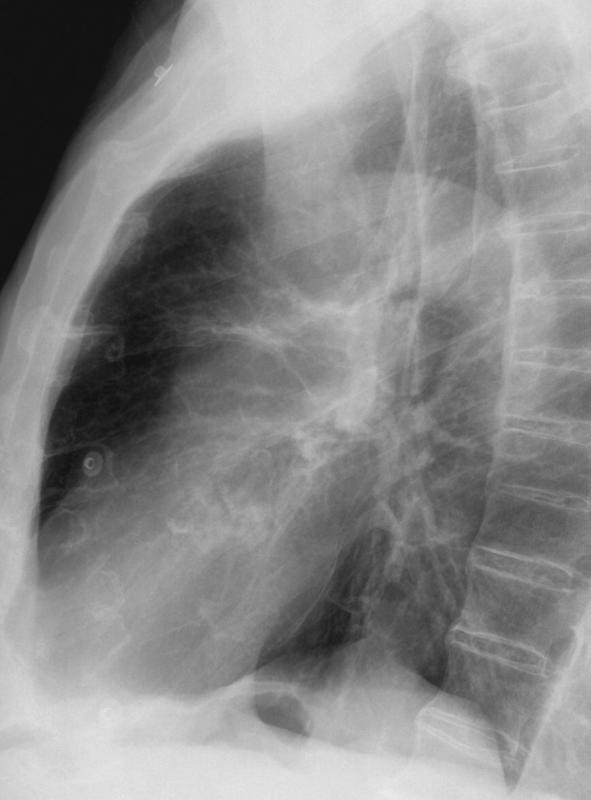

Ao valve calcif (lat only)